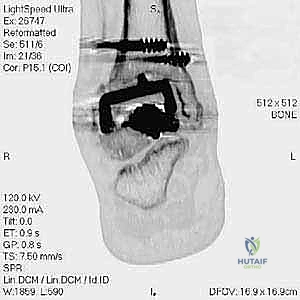

مراجعة مفصل الكاحل الصناعي هي إجراء جراحي ضروري لمعالجة المشاكل التي قد تنشأ بعد الجراحة الأولية، مثل كسور الكعبين أو عدم استقرار المفصل. يتضمن العلاج التشخيص الدقيق عبر الأشعة السينية والتصوير المقطعي، يليه التدخل الجراحي لتثبيت الكسور واستعادة وظيفة الكاحل، مع التركيز على التعافي المبكر.

تُعد جراحة مراجعة مفصل الكاحل الصناعي (Revision Total Ankle Replacement) من الإجراءات الجراحية المتقدمة والبالغة الدقة في عالم جراحة العظام الحديثة. لا تقتصر هذه الجراحة على مجرد استبدال مفصل تالف بآخر جديد، بل هي عملية إنقاذ معقدة للغاية تهدف إلى معالجة المشاكل الميكانيكية والبيولوجية التي تنشأ بعد الجراحة الأولية. من أبرز هذه المشاكل: الفشل الميكانيكي للمفصل، تحلل العظام (Osteolysis)، أو حدوث كسور معقدة في الكعبين (Malleolar Fractures) المحيطة بالمفصل الصناعي. يتطلب هذا الإجراء تقييماً سريرياً وشعاعياً دقيقاً يشمل التصوير المقطعي ثلاثي الأبعاد والأشعة السينية، يليه تدخل جراحي دقيق لاستعادة التوازن الحيوي والميكانيكي للكاحل والحفاظ على الطرف من البتر أو الدمج.

- الأشعة السينية مع تحميل الوزن (Weight-bearing X-rays): لتقييم الزوايا الميكانيكية وتحديد مدى هبوط المفصل أو وجود كسور في الكعب.

- التصوير المقطعي المحوسب (CT Scan): وهو الأداة الذهبية لتقييم "المخزون العظمي" (Bone Stock). يوضح بدقة حجم الأكياس العظمية ومقدار العظم المفقود الذي سيحتاج لترقيع.

* دمج الكاحل (Ankle Arthrodesis): إذا كان التآكل العظمي هائلاً ولا يسمح بتركيب مفصل جديد، يتم إزالة المفصل الصناعي ودمج عظمة الساق مع عظمة الكاحل باستخدام مسامير وصفائح معدنية وطعوم عظمية.

كسور الكعبين (Malleolar Fractures) المصاحبة للمفصل الصناعي

من أعقد التحديات التي تواجه جراحي العظام هي حدوث كسور في الكعب الداخلي (Medial Malleolus) أو الخارجي (Lateral Malleolus) في وجود مفصل صناعي. تحدث هذه الكسور لعدة أسباب:

علاج هذه الكسور يتطلب مهارة فائقة من الدكتور محمد هطيف، حيث يتم استخدام تقنيات الجراحة الميكروسكوبية وتثبيت الكسور باستخدام صفائح معدنية دقيقة ومسامير (Locking Plates) دون المساس بثبات المفصل الصناعي، أو يتم دمج علاج الكسر ضمن عملية مراجعة المفصل الكلية إذا كان المفصل نفسه تالفاً.

يتم إدخال المفصل الجديد المخصص للمراجعة، والذي يحتوي غالباً على سيقان (Stems) تدخل عميقاً في عظمة الساق وعظمة الكاحل لضمان الثبات الميكانيكي. في حال وجود كسور في الكعب، يتم تثبيتها في هذه المرحلة.